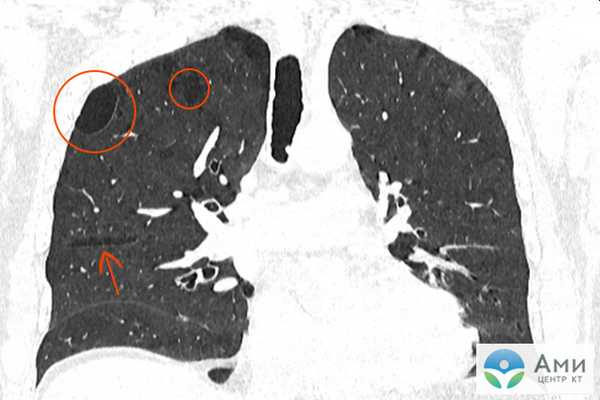

Диагностика буллезной эмфиземы легких основывается на клинических, функциональных и рентгенологических данных. Курация больного осуществляется пульмонологом, а при развитии осложнений - торакальным хирургом. Рентгенография легких не всегда эффективна в выявлении буллезной эмфиземы легких. В то же время, возможности лучевой диагностики существенно расширяет внедрение в практику КТ высокого разрешения. На томограммах буллы определяются как тонкостенные полости с четкими и ровными контурами. При сомнительном диагнозе удостовериться в наличии булл позволяет диагностическая торакоскопия.

Буллы в легких на КТ

Буллы в легких на КТ визуализируются как отчетливые, сравнительно более затемненные пузырькообразные участки легочной ткани, напоминающие дыры или крупные поры губки. Чем более плотная ткань, тем более она светлая на КТ-сканах — поэтому, например, кости белые, а воздушная легочная ткань сравнительно однородного графитно-серого цвета.

На КТ легких врач-рентгенолог может точно определить диаметр булл, их количество, выяснить, есть ли признаки эмфиземы, бронхоэктазы либо иные диффузные легочные заболевания.